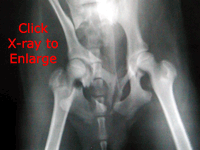

The male pup was rushed into emergency surgery. Aldine had a ruptured intestine, about a foot of which was already dying and had to be removed. He had half a dozen broken ribs, along his back bone rather than the rib cage itself. Both his hips were badly fractured and separated. Naturally he was bruised and scraped everywhere.

Aldine still had blood and fluids filling his lungs that he would be spewing a few days. Organs would swell from internal bruising. His stomach was full of "stuff" that looked like garbage in the x-ray and probably was. And everything in Aldine's stomach still had to pass through the repaired intestine. Aldine's protein levels were very low from his blood loss, so we feared even if he made it through the night... he wouldn't heal properly. At best he would heal slowly. If the surgery didn't "take" and the intestine ruptured again, he would die. His prognosis for survival was very poor. Only time would tell?

What a day! The consultation with the specialist went well and we have decided to have the hip surgery on Aldine. Actually the deciding vote was Aldine himself.. he refuses to just lay around any more and even tried to jump up on the doctor as a greeting. He wants so badly to play and be active that we feel his hip won't heal as well without the pin to stabilize him. His surgery is scheduled for next Tuesday and we can pick him up on Wednesday if all goes well.

Aldine went through his hip surgery with flying colors. The specialist also managed to do the surgery for less than the original quote and still add a neuter!

Aldine's first check up went well and he is due his last check (with new x-rays) next month. He walks well and uses both his rear legs easily. He also moves pretty quicky if you don't watch him closely enough. Aldine did suffer a few days of diarrhea earlier this month, but some quick medicine got him past that and back to normal. We have new pictures of Aldine, but those will have to be added later.